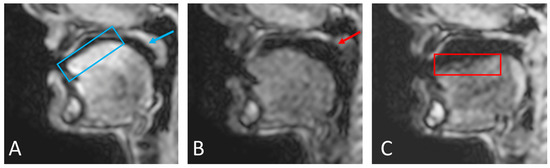

- Manually select a region containing each speech articulator. It must be sufficiently large to allow for a full range of movement of an organ of interest (such as the velum or tongue) and is outlined directly onto the image.

- Automatically segment and create a mask for each organ of interest at each time point, using the Hadamard product of the head mask and organ of interest mask at each time point, an example for the velum can be seen in Figure 3. This results in binary masks for each of the speech organs of interest for each frame in the original dynamic image set.